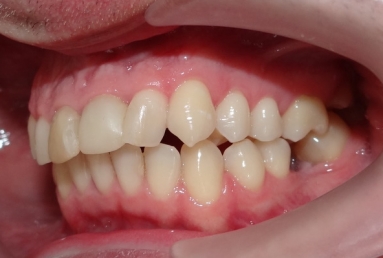

The orthodontic treatment was necessary as the upper maxillary developed assimetricaly, also the teeth were malpositioned. The purpose of the partial braces was to help the final prosthetic treatment, which consisted of two full ceramic crowns for the central incisors, that had root canal treatments, and a ceramic veneer for the lateral incisor, that had a large composite filling. Gingivectomies were also necessary for the right canine and incisors in order to correct the assymetrical gummy smile.